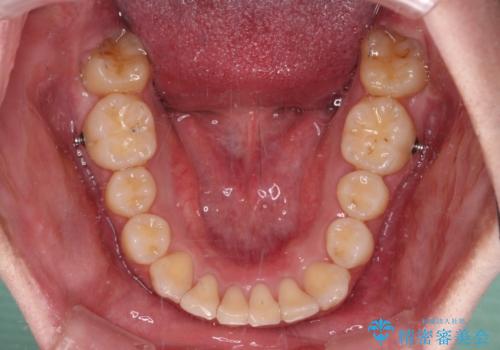

ディープバイトや奥歯の咬み合わせなど、インビザライン矯正では限界がありワイヤー装置での治療に及ばない仕上がりとなりました。

ただし、患者様としては八重歯や、それに伴う唇の閉じにくさが改善されたとのことで、納得いく状態での治療終了となりました。